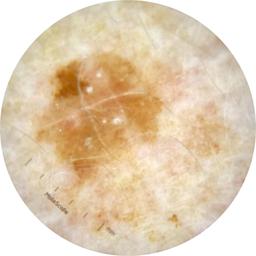

ISIC_8490164

Field Value

acquisition_day 218

age_approx 65

anatom_site_1 Upper extremity

anatom_site_general upper extremity

concomitant_biopsy False

diagnosis_1 Benign

diagnosis_confirm_type single image expert consensus

family_hx_mm True

fitzpatrick_skin_type I

image_manipulation instrument only

image_type dermoscopic

lesion_id IL_9551927

patient_id IP_2259625

personal_hx_mm True

sex female